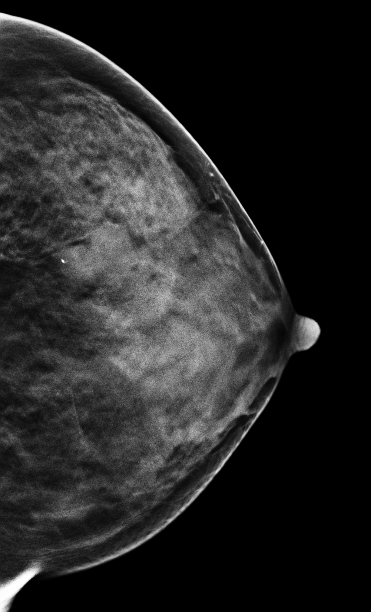

病史:患者,57岁,左乳乳腺癌术后,右乳发现肿块2月余。

2D图像:

在常规2D图像右乳外上象限隐约见一不规则团块影,部分边界模糊(容易漏掉),边缘可见粗大钙化灶,在V-Preview图像MLO位和CC位上团块显示较模糊,但钙化清晰可见,在3D-slab图像上我们可以清晰见到病灶呈分叶状改变,边缘可见蛋壳样钙化灶,周边见细线样透亮环。从以上细微征象我们可以初步判断是一良性病灶。

左乳外上不规则肿块,考虑良性病变,BI-RADS 3级。

病理证实左乳纤维腺瘤,此病例我们可以发现3D-Slab(厚层图像)对钙化灶形态大小显示更加清晰。